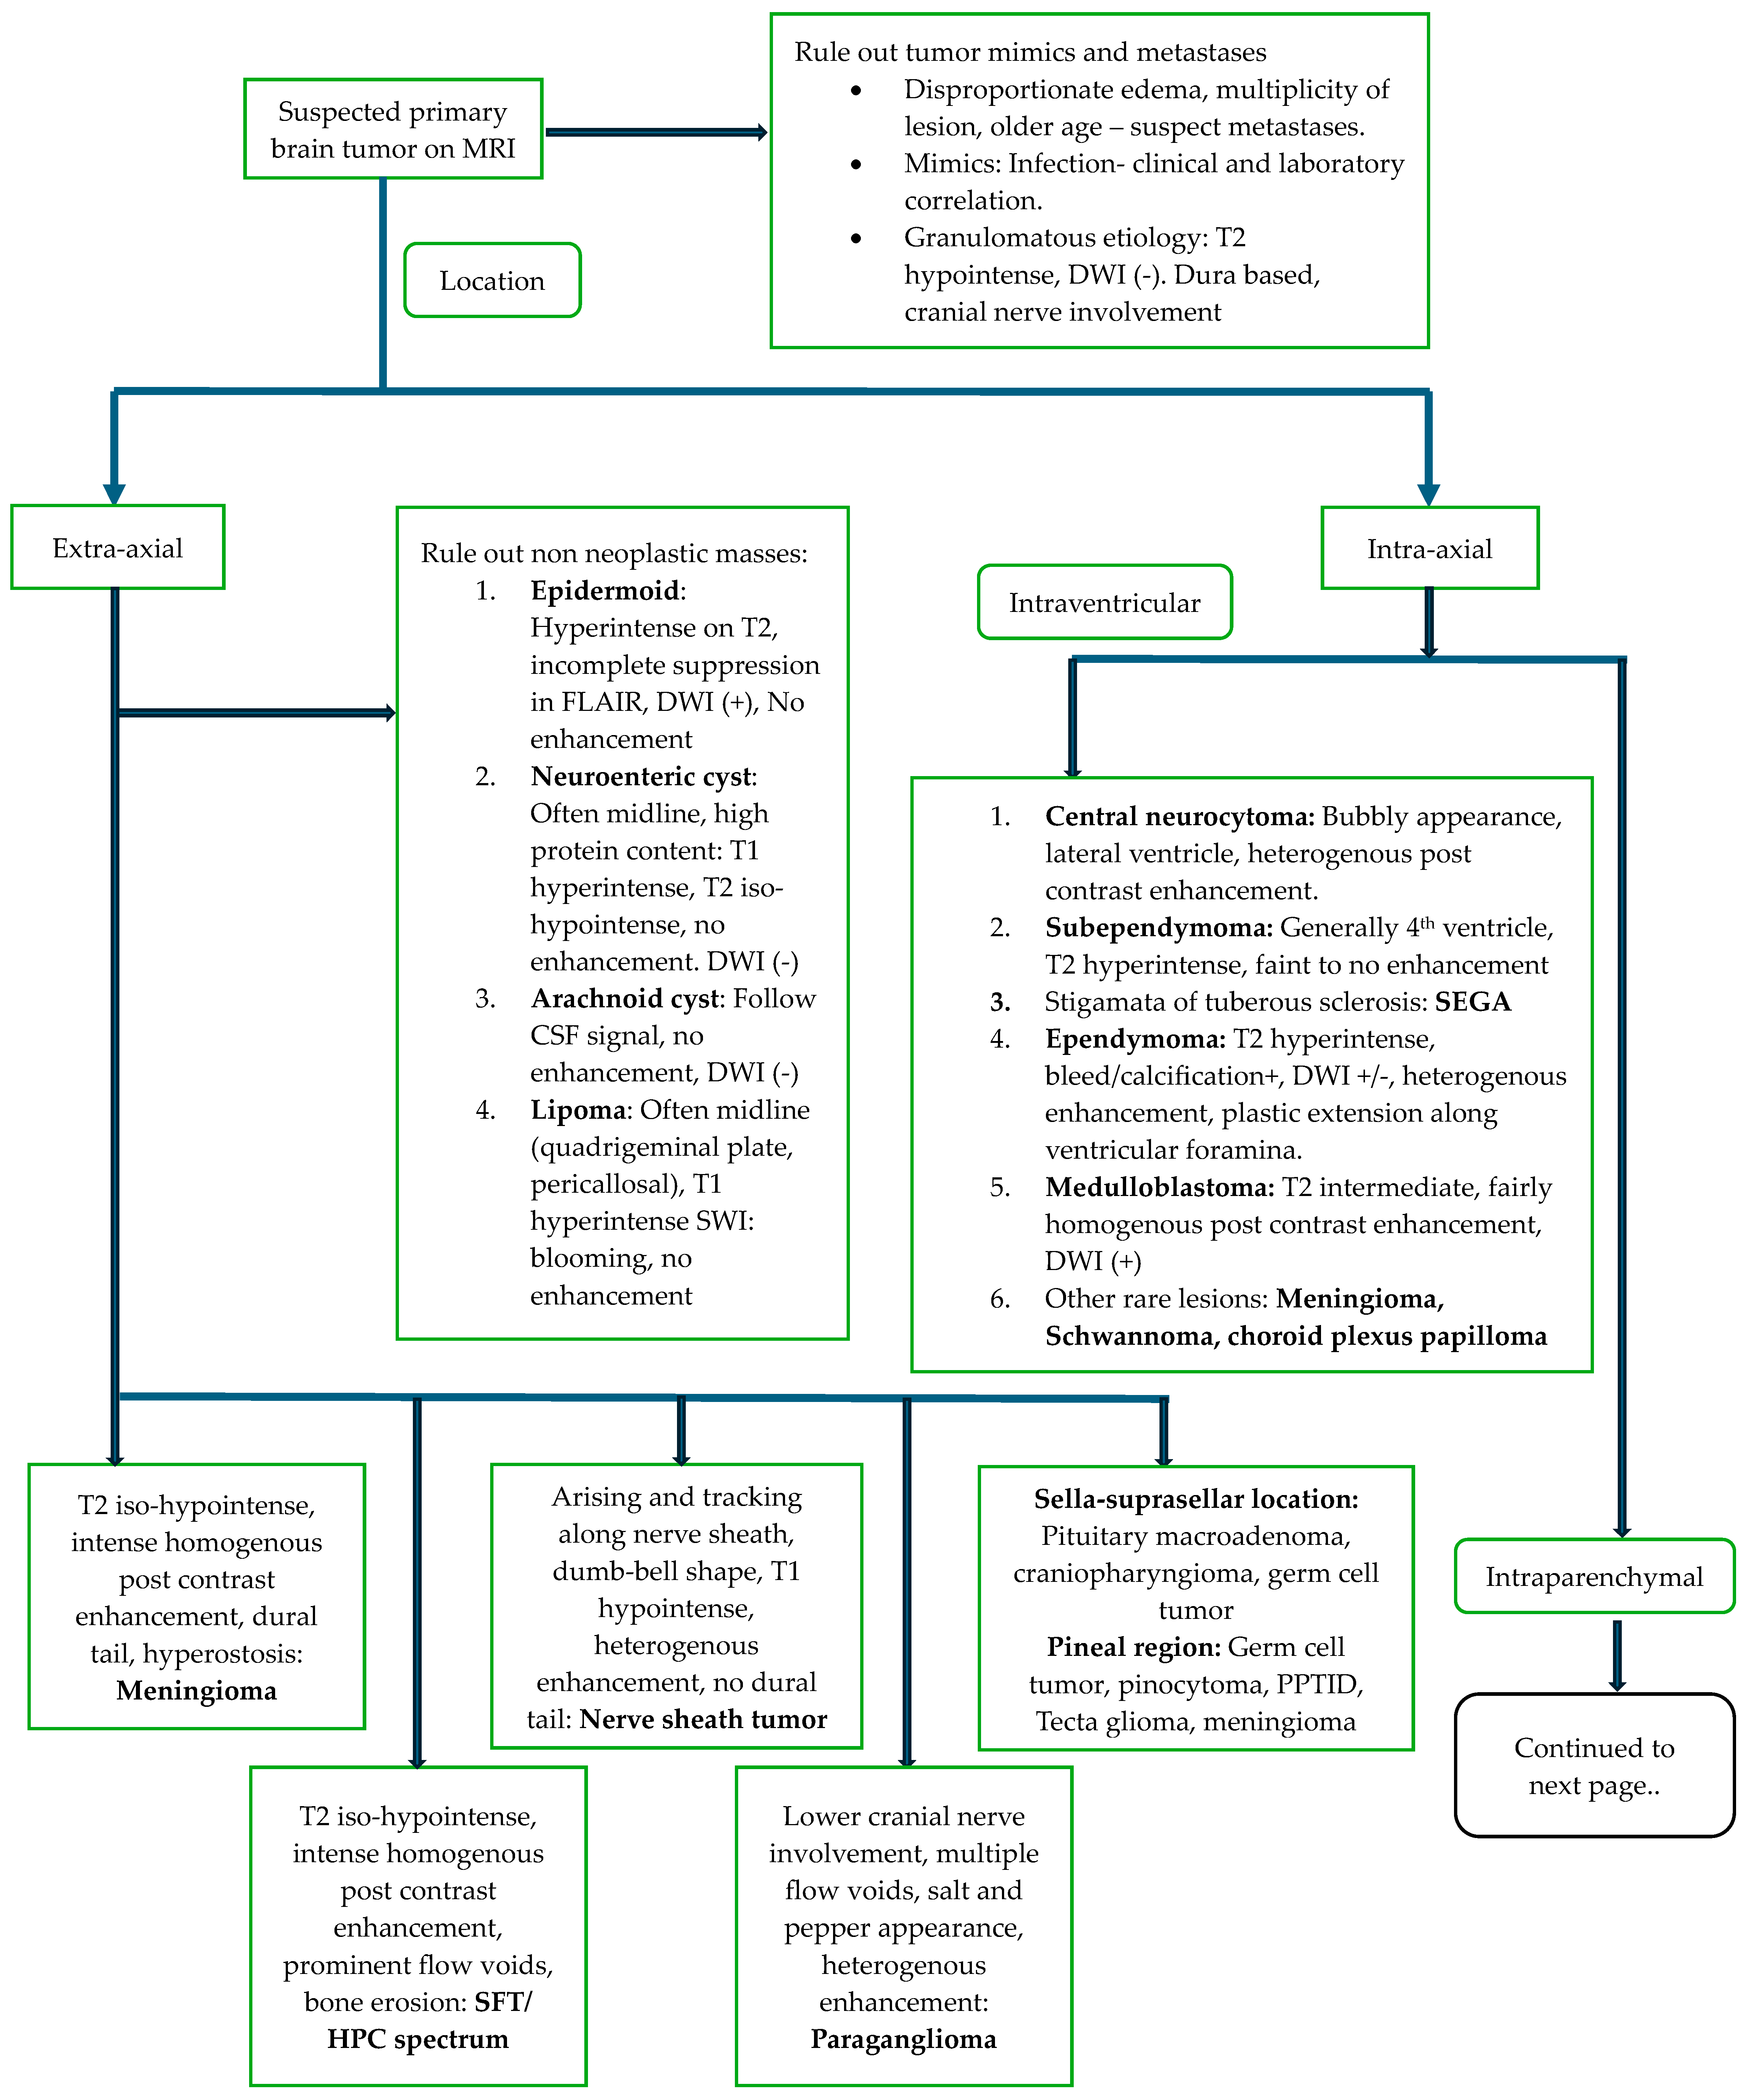

5.2. Diagnosis